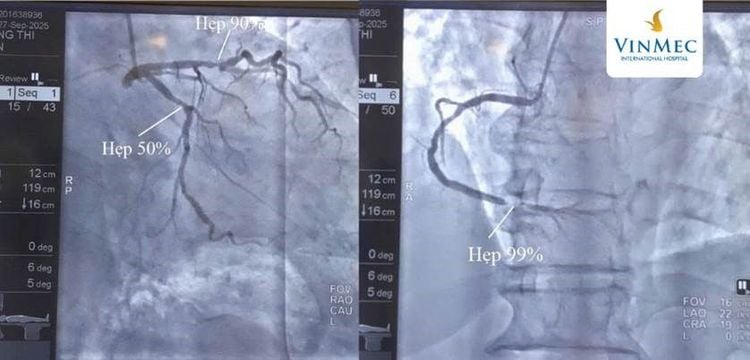

Kết quả chụp động mạch vành cho thấy bệnh nhân có tổn thương nặng ở cả 3 nhánh động mạch vành:

• Hẹp 99% động mạch vành phải (RCA, đoạn 3)

• Hẹp 90% động mạch liên thất trước (LAD, đoạn 2)

• Hẹp 50% động mạch mũ (LCX, đoạn 2)

Đây là tình trạng tắc nghẽn nghiêm trọng, nếu không được tái thông kịp thời có thể gây ngừng tim, đột tử. Sau khi hội chẩn nhanh, các bác sĩ quyết định tiến hành đặt stent can thiệp để mở rộng các đoạn mạch bị hẹp nặng. Trong vòng 50 phút, ê-kíp đã đặt thành công 1 stent vào RCA và 1 stent vào LAD, tái thông mạch máu, đảm bảo dòng máu trở lại nuôi tim.